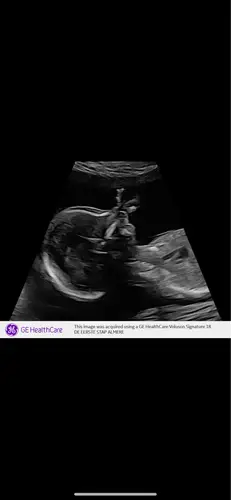

Wij hebben bij de 20 weken echo te horen gekregen dat onze dochter een te kleine onderkaak heeft (micrognathie) en hebben afgelopen maandag een vruchtwaterpunctie gehad plus bloedonderzoeken. In onze families komen zulke afwijkingen niet voor en ook geen syndromen. De klinisch geneticus gaf aan dat er maar 5% kans is op een syndroom maar de uitslag horen we pas over 3 weken. Er zijn verder ook geen andere lichamelijke afwijkingen gevonden. Ik heb zelf op 17 jarige leeftijd een kaakoperatie gehad omdat deze iets naar achteren stond maar bij de geboorte was dit niet bekend. Wellicht heeft ze dat dus van mij geërfd. Er was een mooie maaginhoud te zien bij onze dochter en de slokdarm functie deed het ook goed. Het is allemaal zo onzeker en we maken onszelf helemaal gek met de ergste scenario’s. Er is nog niks bekend alleen de mircognathie is wel vastgesteld. Het kan dus gaan om alleen een cosmetisch probleem (waar wij natuurlijk op hopen) of om een syndroom, al is die kans klein. Hebben jullie misschien wat ervaringen en vooral geruststelling voor ons?